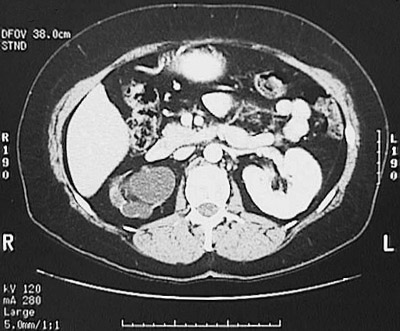

This abdominal CT scan with contrast demonstrates marked right hydronephrosis as a consequence of ureteral obstruction.